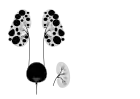

Adult polycystic kidney

Diagram of autosomal dominant polycystic disease with a normal kidney inset for comparison